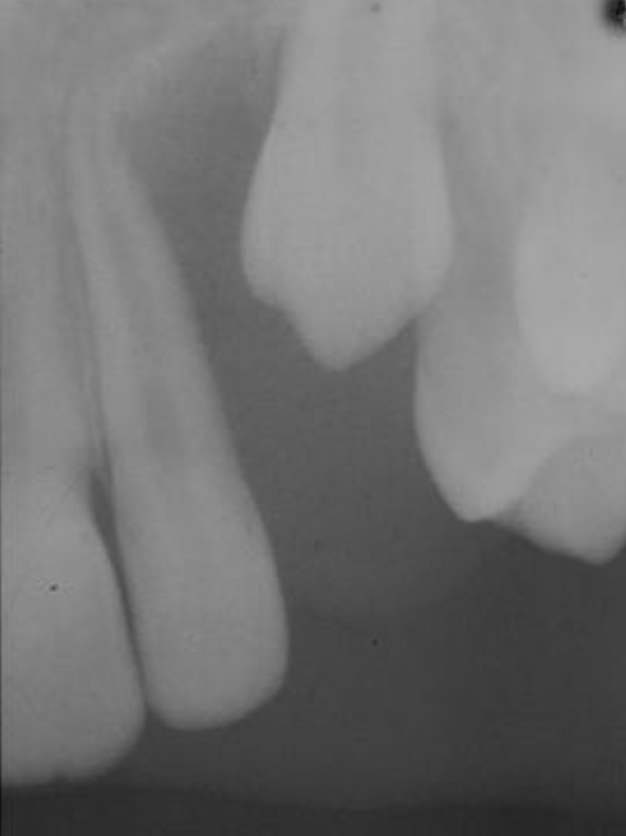

8

A

dentigerous cyst